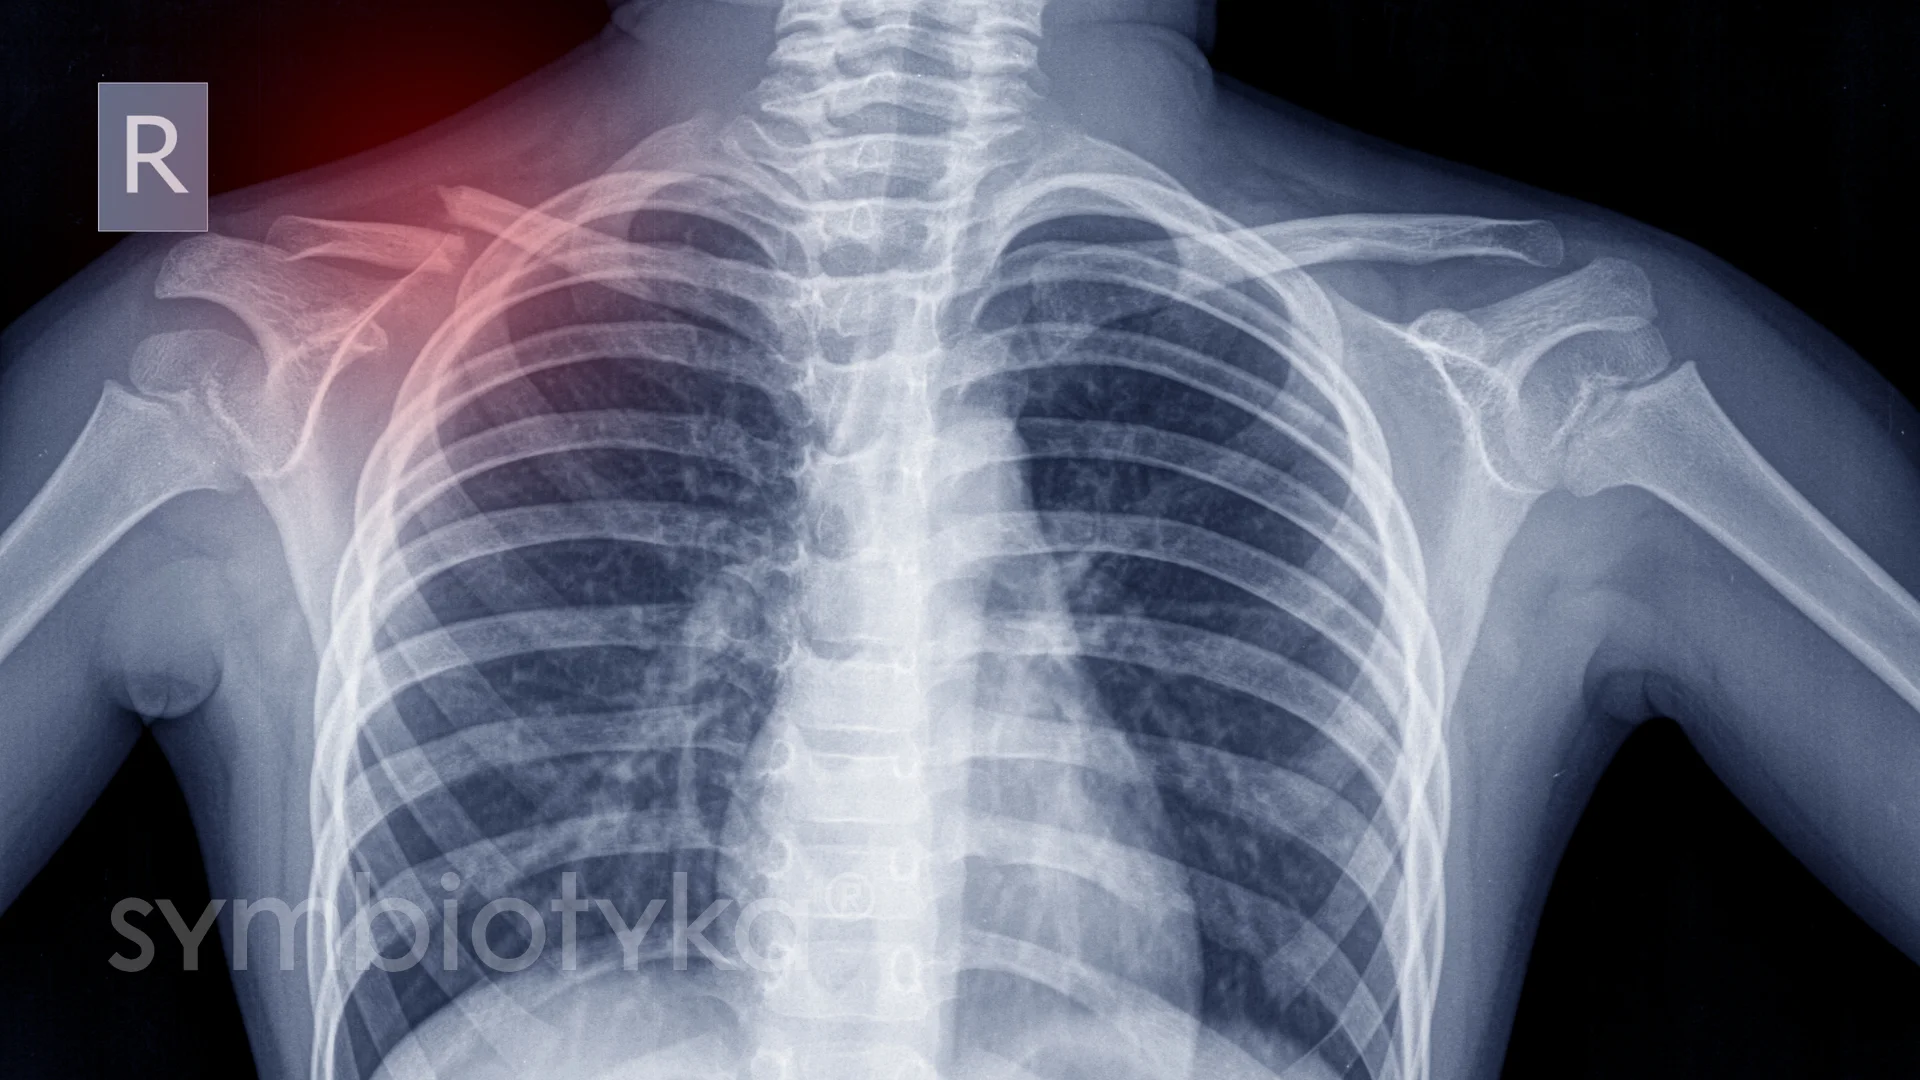

- Рентген

Рентген

Класика жанру. Швидко і надійно допоможе виявити переломи чи вивихи.